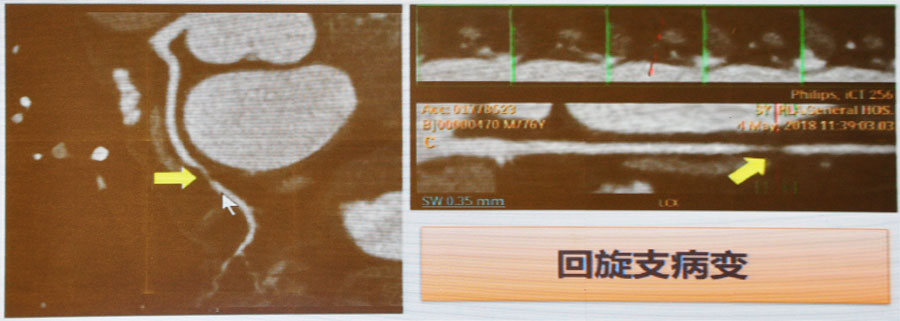

3. 冠脉CT(CTA)

可判断冠脉官腔狭窄程度和管壁钙化情况,有较高的阴性预测价值(99%)。优点是简单、快速、无创;缺点是受心率、钙化等因素限制。

图5 回旋支病变